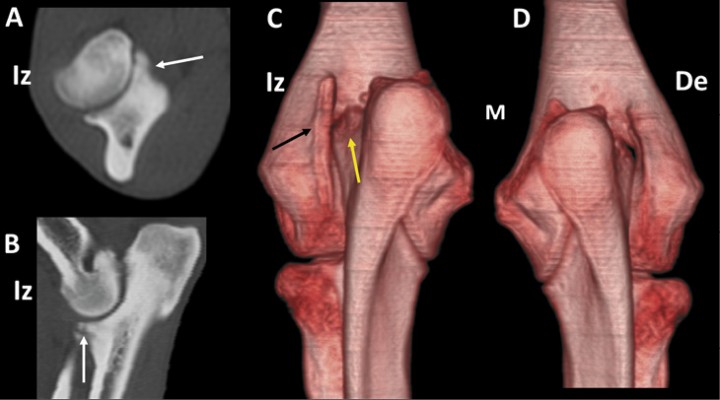

Figura 2

Labrador Retriever macho de 5 meses, con cojera unilateral intermitente del codo izquierdo. Imagen en 3D del codo, en vista caudal (A) y planos dorsal (B), sagital (C) y transversal (D). Osteocondrosis del cóndilo humeral, con abundante hueso esclerótico (flechas negras) y un fragmento osteocondral desprendido del cóndilo (flecha amarilla). Se señala la fragmentación de la apófisis coronoides medial del cúbito (flecha blanca). Existe artrosis avanzada, especialmente manifiesta en la cara medial del codo (M).